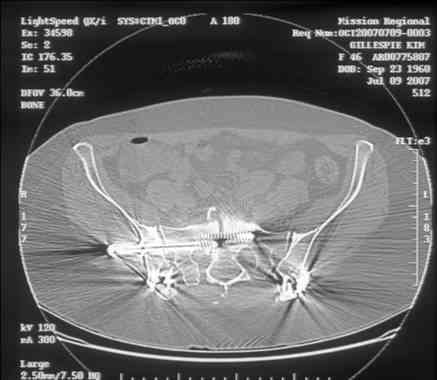

Re: Sacral Non-Union

David Zamorano 25 Август 2007, 21:05

Here is a magnified view. Sorry about the quality but the CT was scanned into our system.

dave

Отправитель: Chip Routt 25 Август 2007, 21:08

Thank you...it might help to remove the disengaged and other iliosacral screws then insert longer lag screws into the upper sacral segment and if anatomically feasible into the second sacral segment as well.

You could do it percutaneously and even add an electrical stimulation device if that seems reasonable.

At this point, I'd ignore the right pubic root issue if asymptomatic.

If simple measures such as those above fail, then you could remove it all, take down the sacral fracture site, refix with alternate techniques, and bone graft.

Chip